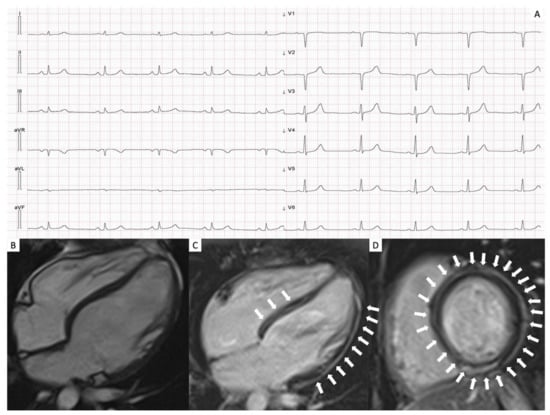

3.2. Electrocardiographic Findings

3.4. CMR Findings